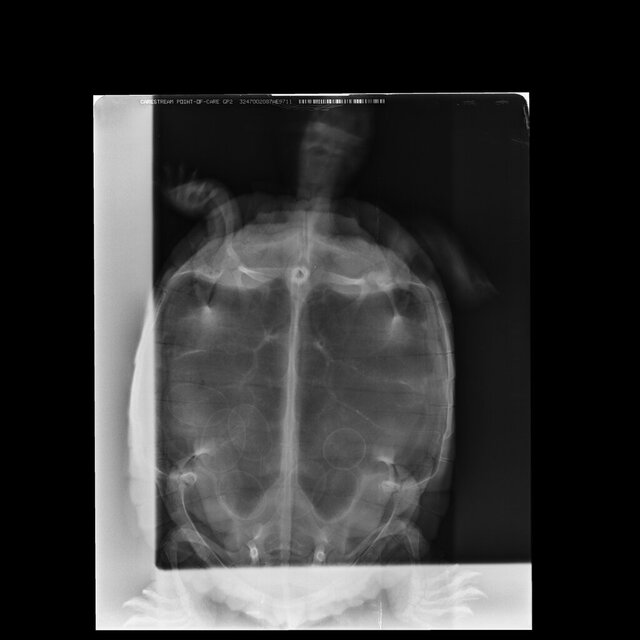

9.Обращались ли в ветклинику? Как называется ветклиника? Как зовут врача (ФИО)? Вводились ли какие-то препараты, если да, то в каких дозировках? Что было сделано по рекомендациям врача? Герпетологов в городе нет, делали рентген, яйца есть.

22a7d346-fe2c-41b3-834c-e9f7e0750714.JPG

@moth 17.01 после курса уколов черепаха снесла 10 яиц, хотя на первоначальном снимке их было 7.

18.01 сделали контрольный снимок, на снимке оставшихся яиц не видно, либо рентген слишком мощный и он просветил все насквозь.